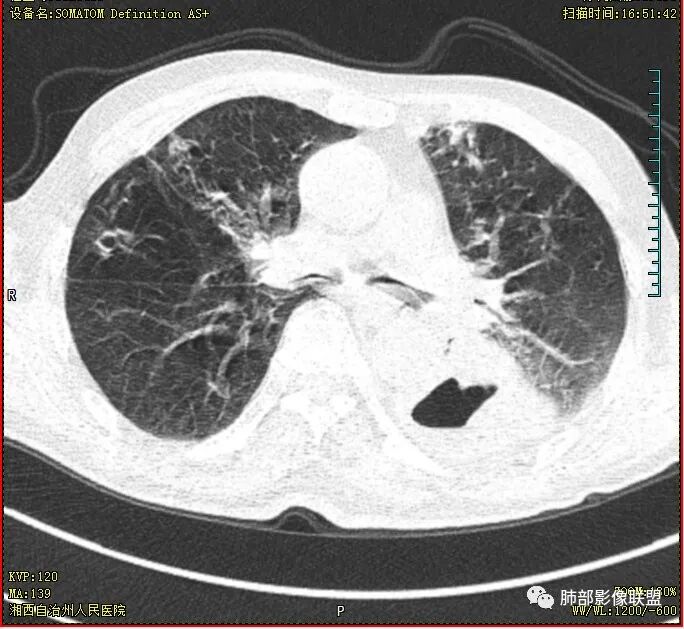

抗炎3周洞臂缩小

18号复查肺窗空洞显示不清,20号用了俯卧位扫描,液体向下流动空洞又显示出来了。

首先双肺多灶多形态病灶,考虑结核,聚焦左下肺病灶,空洞,内壁尚光整,有明显液化坏死,增强无明显强化,壁内可见支气管充气征,复查后空洞缩小,首先考虑良性,结核伴脓肿,鉴别鳞癌

胸部CT:双肺多发小斑片、树芽、索条灶,左下肺大片不均质实变,远肺门侧厚壁空洞,气液平,内壁有坏死物残留,增强可空洞壁不均匀强化,近端支气管壁不规则增厚堵塞,实变影内可见与洞壁平行支气管。抗炎3周有缩小。

2.患者发热,中性粒细胞等炎性指标轻度升高,C-反应蛋白高,短期内双肺病灶吸收明显,吸收部分较符合普通感染性病灶,也可以因部分肺泡积血有所吸收。

3.注意到左肺下叶空洞性病灶,腔壁厚度不均,环形强化较为明显,壁间支气管血管影走行,腔内液气平面,这通常见于感染性病灶,如脓肿,经治疗病灶吸收也高度支持病灶主体成分为脓肿。